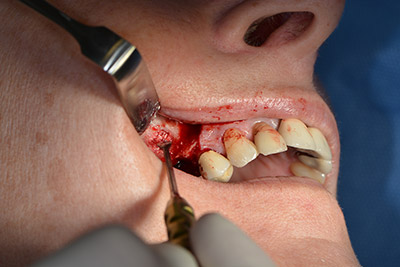

The implant was then placed and the bone built up. In this case, because of the size of the augmentation region, autologous bone chips, harvested with an osseous trap as drilling chips from implantation 16 and fenestration 14, were mixed with bone replacement material.

An absorbable membrane was used as the barrier in the buccal direction and covered the augmentation. Finally, saliva-proof sutures were placed (Fig. 15 to 19).